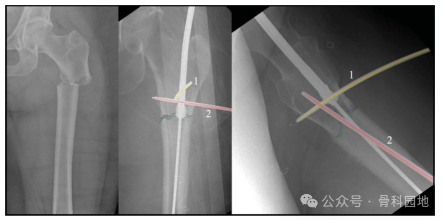

适当的进针点和适度的扩髓可以矫正成角畸形。进针点偏外导致内翻复位不良,在需要扩髓的髓内钉,转子下区与股骨近段相连的部分,如果扩髓不充分,可作为一种变形力(如下图)。外侧皮质会导致内翻畸形,内侧皮质则会导致外翻畸形。